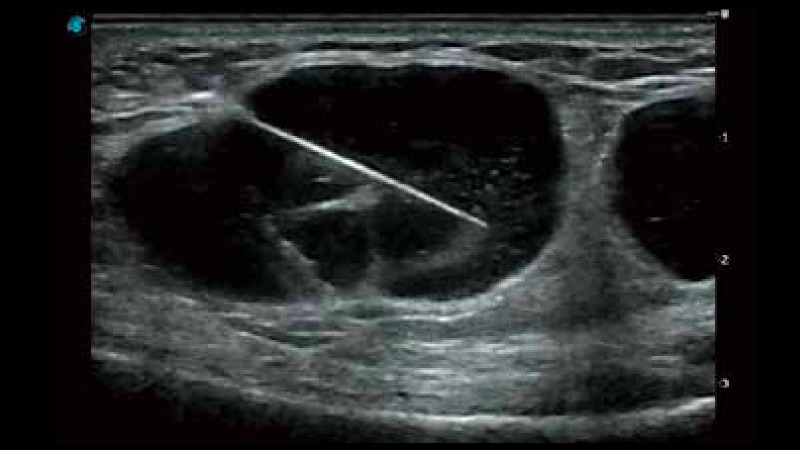

開立醫(yī)療通過不斷的技術(shù)創(chuàng)新,為大眾的生命健康提供持續(xù)關(guān)愛。P12 Plus采用全新一代超聲成像平臺,新平臺旨在將真實(shí)還原組織解剖結(jié)構(gòu)作為首要目標(biāo)。平臺采用全新集成化硬件模塊,搭載新一代芯片,系統(tǒng)性能得到大幅提升,為您的診斷提供了豐富的臨床信息。優(yōu)異的圖像表現(xiàn),豐富的探頭配置,全面的應(yīng)用功能,為您日常診斷提供了可靠的助手。

P12 Plus

彩色多普勒超聲診斷系統(tǒng)